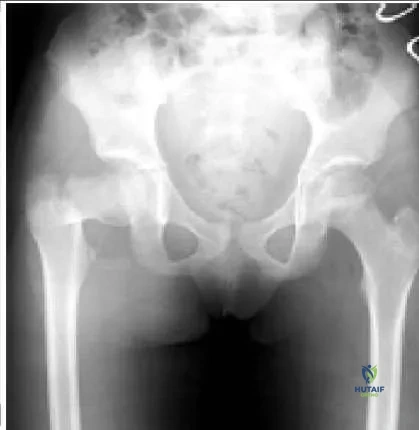

A 9-year-old girl sustains an injury (Slide) as a result of a fall. What is her risk of avascular necrosis:

This patient has a displaced basicervical fracture of the femur that is classified as Delbet type III. The risk of avascular necrosis is approximately 20% to 25%. She should be monitored closely for the first 12 to 18 months after injury for this complication.